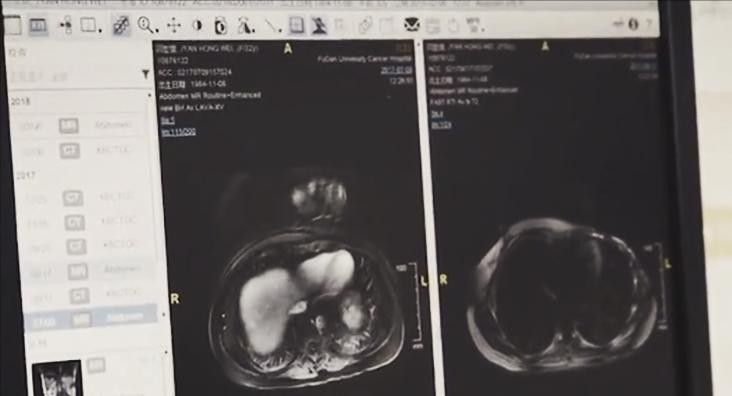

由于美国的检查结果推翻了之前的诊断,医院为了保险起见,对闫宏微做了全身扫描。

全身扫描的结果显示,闫宏微的癌细胞在持续恶化,肺部的病灶超过3个,依然呈现阴性。

这说明,闫宏微在美国的检查并不全面准确。